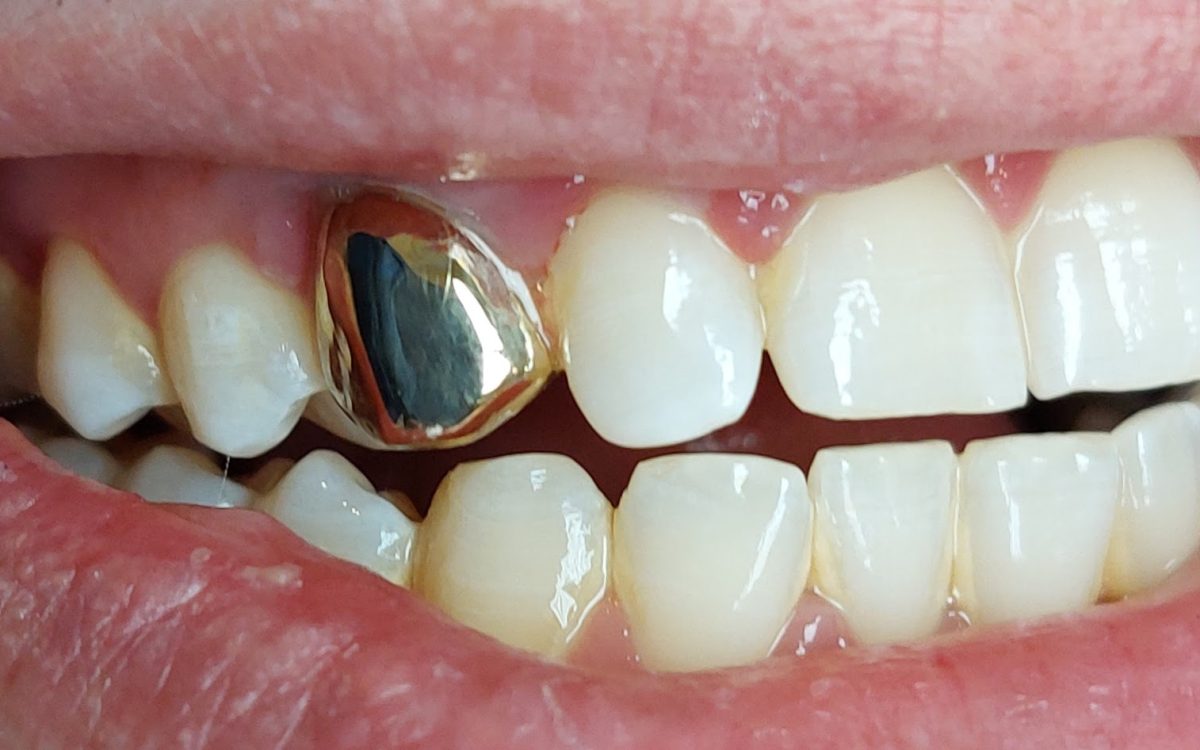

Korona és hídpótlások, kivehető pótlások

Fogászati korona

Hiányzó, sérült, vagy szuvasodott fogak pótlásának, helyreállításának egyik hagyományos és igen elterjedt eszköze a fogkorona.

Hogyan készül?

A fog vagy implantátum előkészítése után lenyomatot veszünk, melyet elküldünk a fogtechnikusnak, aki megkezdi a fogpótlás elkészítését az általunk választott anyagból. A pótlás elkészülése közben egyes munkafázisokban próbákat végzünk a pontosság és az esztétika megítélésére és tökéletesítésére. Az előkészítés és a korona átadása közötti időben sem hagyjuk a pácienst “fogatlanul”, ideiglenes koronával törekszünk a kezelések közötti fogérzékenységeket csökkenteni és az esztétikát fenntartani.

Ha a próbák sikeresek és a páciens is elégedett, a kész munka végleges rögzítésre kerül.

Típusai:

Porcelán (fémkerámia) fogkorona

Fémkerámia korona előnyei:

- Kedvező ár/érték arány: a fémkerámiából készült fogpótlás a legkevésbé terheli meg a pénztárcát, és jó alternatíva a régi, alászuvasodott koronák vagy híd cseréjére.

- Esztétikus: ma már a fémkerámia fogpótlás színe is lehet olyan, mint a meglévő fogaké.

- Modern technológiával történik az előkészítés: a régi fémkerámia koronák egy idő után elkezdték irritálni az ínyt, ami begyulladt és a korona és a fogíny találkozásánál szürke ínyszél alakult ki. Ma már vállas előkészítést alkalmazunk, aminek a lényege, hogy az íny helyett a fogra támaszkodik a korona, így elkerüljük az évek múlva kialakuló csúnya hatást.

- Tartós, stabil, strapabíró: A fémkerámia pótlásnak a váza fém, a felszíne kerámia. A fémvázat évtizedek óta alkalmazzuk a fogorvoslásban, jó technológiával készítve sokáig biztonsággal haraphat elkészült koronáin.